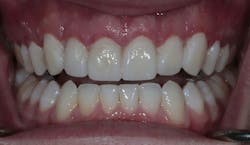

New scans of the patient’s mouth were taken eight weeks after the osseous surgery, prior to the minimal veneer preparations. The original digital plan then can be evaluated, which typically involves minor changes. The next phase design would be printed in the office following sharing the STL files (stereolithography). This allows the office to create a restorative matrix and reduction guide for the dentist. Careful preparation was utilized so as to stay within enamel only, which many studies have shown allows for more predictable bonding and longevity of veneer restorations. Standard tissue retraction methods were used, and the preps were scanned with iTero 5D Plus. The provisionals created from the digital plan would allow the patient to test-drive the new smile prior to the final 10 porcelain restorations being placed. The patient was seen a few days after his preps to allow any modifications before the final 10 e.max pressable veneers were created.

After experiencing the comparative advantage the provisional teeth offered him, the patient was ready for the final restorations to be placed. After placement, the patient left the office with both an esthetic and functional upgrade to take on life after college with confidence, featuring 10 porcelain veneers across his maxillary teeth.

As a review, the digital approach greatly enhanced an outcome built upon accurate and predictable surgery, conservative tooth preparation, and tailored esthetics that both enhanced the patient’s natural features and addressed his main concern in an efficient and well-communicated series of steps.